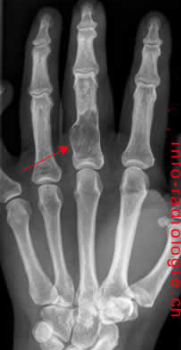

Quelle est la lésion lytique la plus commune des mains et des pieds?

Enchondrome

A

3